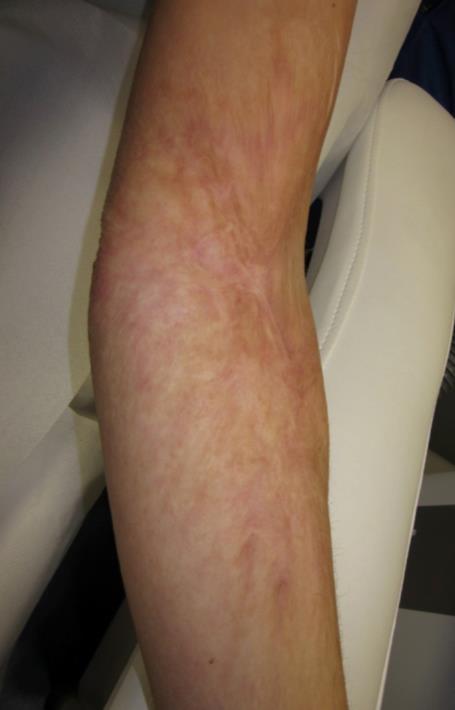

Trước

Hình ảnh minh họa

Sau

Hình ảnh minh họa